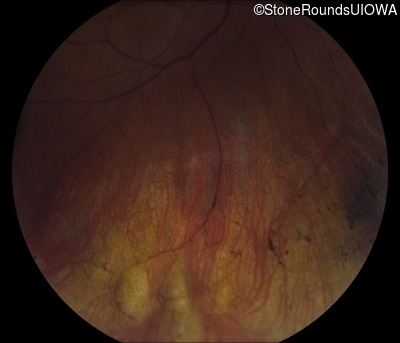

Fundus Photography - Right - 20/30 -2